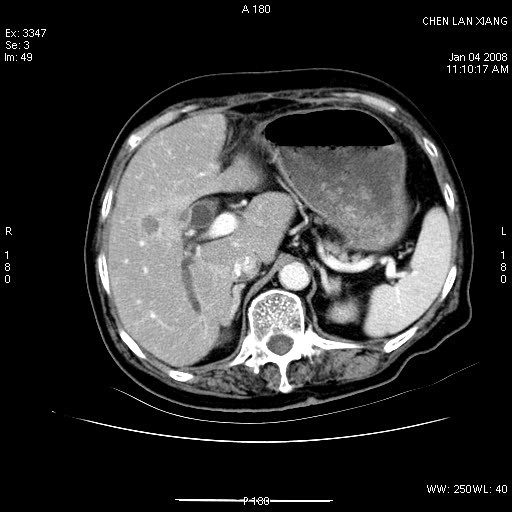

女,76岁,腹痛3-4天,b超示:肝内实性肿物,胆囊强回声,胆总管扩张.

考虑:1、胆总管下端结石伴梗阻性肝内外胆管扩张(肝左叶外侧段肝内胆管多发结石、胆管炎);

2、肿囊癌累及肝,不除外 黄色肉芽肿性胆囊炎。

1 胆总管末端结石伴肝内胆管结石,肝内外胆管扩张。2 胆囊扩大,胆囊壁不规则增厚,内见软组织密度影。考虑:慢性胆囊炎,不除外胆囊癌!

标题: 肝右叶病灶

胆囊癌侵犯肝右叶?

1)胆囊癌伴肝脏转移。2)胆总管下端结石、肝内胆管结石伴肝内外胆管扩张。